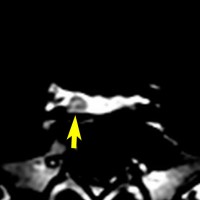

とても小さな腫瘍(微小腺腫) microadenoma

日本で汎用されているものでは最も解像力が高い3テスラMRIで撮影された,ガドリニウム増強像です。左側の画像では下垂体の大きさと形は正常に見えます。画像を調整すると,下垂体の内部,右端(黄色の矢印の先)に6mmくらいの小さな腺腫がみつかりました。MRIの性能がよくなったことによって数mmの小さなものも診断できるようになりました。